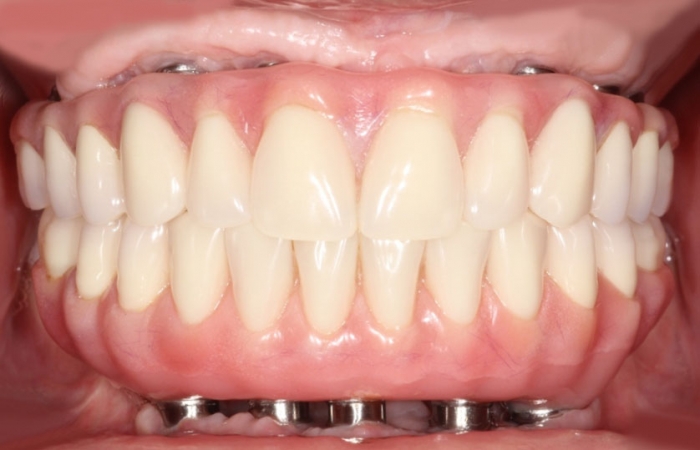

Próteses fixas em resina superior e inferior sobre implantes

Sorriso final do caso terminado em setembro de 2012